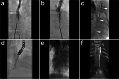

Fig. 7

Illustration of interstitial MRL in a pig model. After interstitial injection of gadoxetate disodium at the bilateral foot dorsal, a dynamic coronal 3D-TWIST scan was performed. Thirty minutes later, the definite thoracic duct (white arrowheads) started from cisterna chyli (white arrow) was visualized (A). Afterwards, a 3D-FLASH scan was performed, which presented the continuous lymphatic network surrounding bilateral iliac arteries and veins (white arrowheads; B) to retroperitoneal lymphatic vessels (white arrowheads; C) and thoracic duct (white arrowhead; D, E). Coronal 3D-FLASH MIP image demonstrated a clear structure of retroperitoneal lymphatic vessels, cisterna chyli (white arrow), and proximal thoracic duct (white arrowheads) (F). Images were from Pig No. 11. Abbreviations: MRL, magnetic resonance lymphangiography; 3D-TWIST, three-dimensional time-resolved angiography with interleaved stochastic trajectories; 3D-FLASH, three-dimensional fast low angle shot; MIP, maximum intensity projection